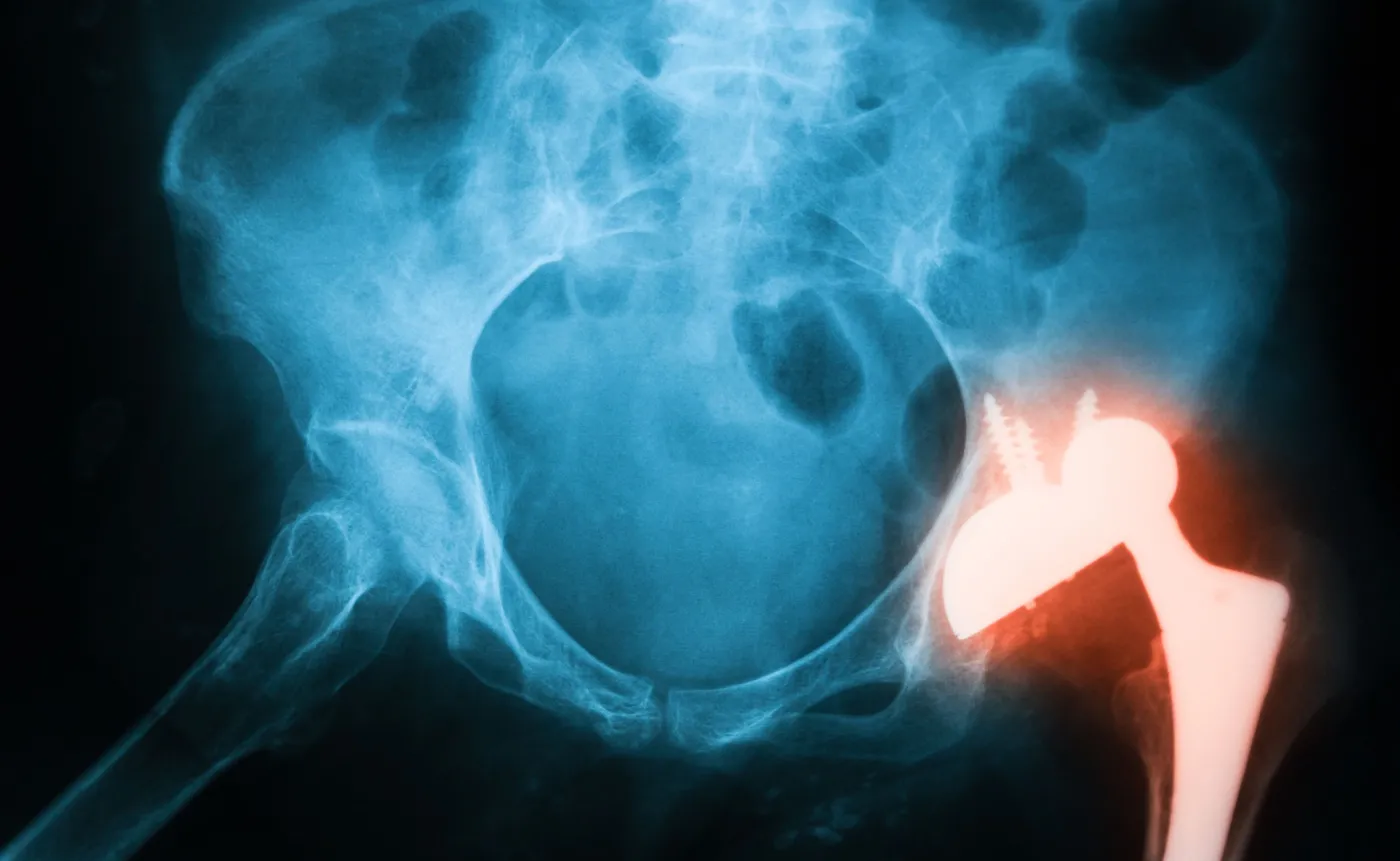

10 maja 2025MedTech Solutions S.A. podpisała strategiczną umowę z GPC Medical Limited – największym indyjskim producentem sprzętu ortopedycznego, w tym implantów kręgosłupa, biodra, kolana oraz systemów do stabilizacji złamań. Polska spółka zyskała wyłączność na dystrybucję implantów w Polsce i szansę na ekspansję w UE.